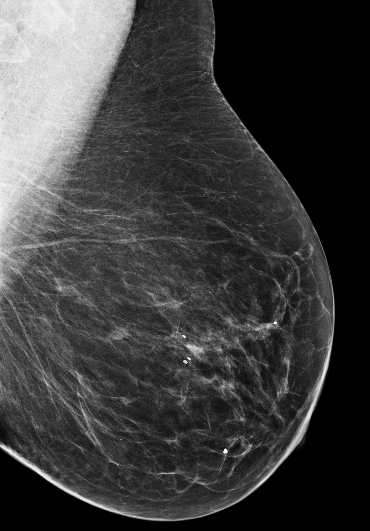

Masking refers to the phenomenon in which a tumor is hidden by the surrounding breast tissue, causing the cancer to be difficult or even impossible to discern with regular mammography, as seen in Figure 2. Masking can also result in large invasive cancers111We define large invasive cancers as those confirmed to have spread and be 2cm at time of diagnosis. – a small cancer may be difficult to discern in certain images, allowing it to grow to a more lethal size. Masking is correlated with breast density, as it has been shown that cancer in dense breasts is more likely to be missed during screening [5, 6, 7]. Density can be subjectively assessed by radiologists via the BI-RADS density standard (ACR) [8, 9], or measured by automated tools such as Libra [10]. These density measurements, however, do not perfectly correlate with masking potential. Radiologists consider the distribution and pattern of tissue when assessing masking potential, and have called for automated methods to assess the masking effect [11]. Until now, the question of exactly how masking potential should be quantified remains an open one, although some subjective notion has been added to certain categories of the most recent edition of BI-RADS density [12].

In this work, we introduce the CSAW-M dataset – a collection of over 10,000 mammographic images and associated masking assessments from experts. The assessments were graded by radiologists according to 8 levels of masking potential, as depicted in Figure 1, from easily assessed mammograms with low-masking potential (level 1) to difficult-to-assess examples with high-masking potential (level 8). This data can be used to train models capable of predicting masking potential from mammographic images in an ordinal classification setting.

The goal of the annotation procedure was to label each image with expert assessments of masking potential. Masking was quantized into 8 bins, or levels, as depicted in Figure 1, for the public training and test sets. Images in the private test set are fully sorted according to masking. Individually sorted examples provide a more granular assessment, but at the cost of increased annotation time. We opted for fine granularity on the private test set because (1) it allows for a more fine-grained assessment, and (2) it allowed us to identify robust initial bins555We use “bin” and “level” interchangeably to denote collections of images with similar masking potential. for the 8 masking levels in the public training/test sets. To represent the initial bins, we chose images personalized to each radiologist, but with highest agreement among the other experts. The benefit to this approach is that the starting point respects subjective assessments while at the same time choosing representative examples for each masking level.